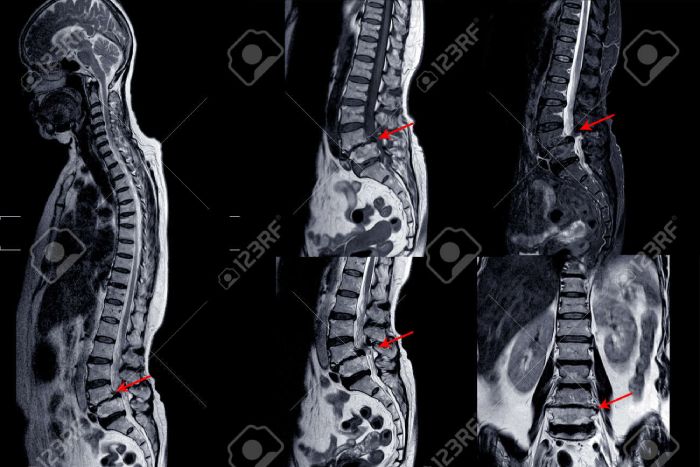

RNM de la columna lumbar que muestra una grave mielopatía medular